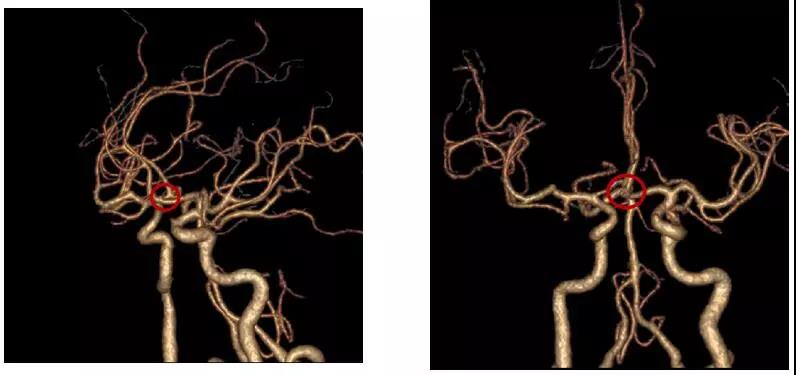

患者术后头部CTA

经过充分的术前准备,李雪松医疗团队仅用了两个多小时就顺利完成手术。术后当天,患者就睁开了双眼,肢体、语言功能等方面都正常,家属脸上露出了满意的笑容。目前,患者正在积极的康复中,不久就能出院。